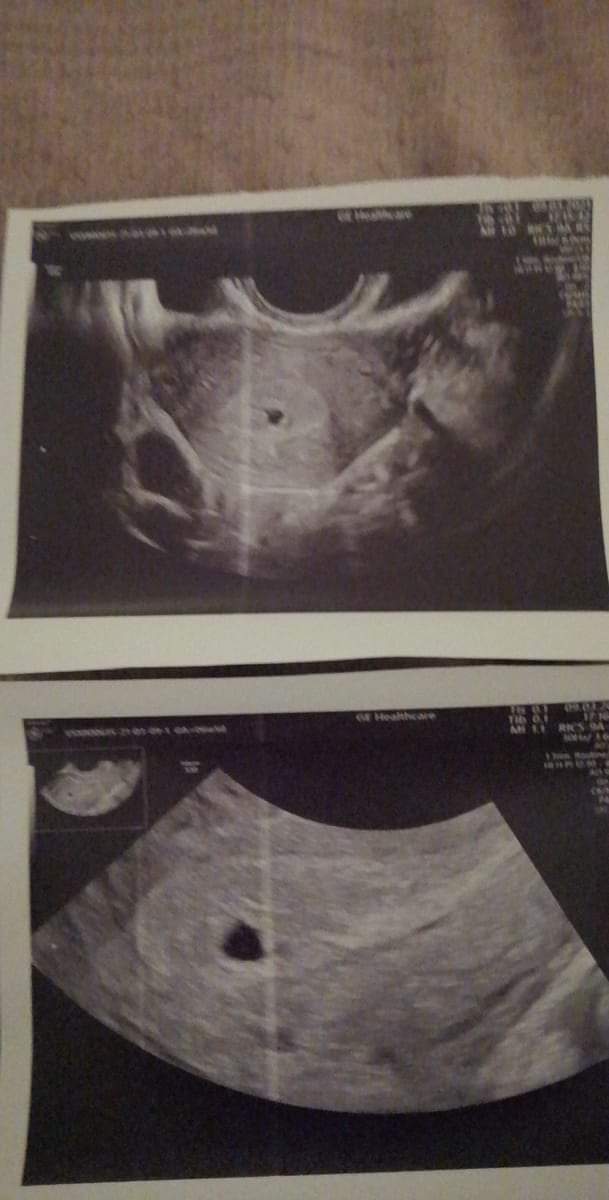

dodaje również zdjęcia z usg, wg lekarza sam pęcherz płodowy..

W dniu wczorajszym wizyta u lekarza tj 9.03 wg obliczen z terminu ostatniej miesiączki 6tydzień + 5 dni. Beta hcg zrobiona w tym samym dniu z wynikiem 681 (powtórzę za 48h żeby sprawdzić czy rośnie). Lekarz niestety na usg nie widział zarodka, powiedział że może to być młodsza ciąża ale powiedział też że nie chce zapeszać i nie zakłada na razie karty ciąży. Kazał przyjmować kwas foliowy i przyjść za 2 tygodnie na wizytę żeby sprawdzić czy coś widać.